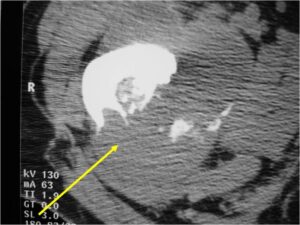

Ill-defined, lytic intraosseous lesion

- Or extraosseous soft tissue mass

- Devoid of calcifications in continuity with lesions having the features of a cartilaginous tumor

Characteristically abrupt transition between chondroid tumor and dedifferentiated, lytic component

Bone may be expanded and adjacent cortex thickened